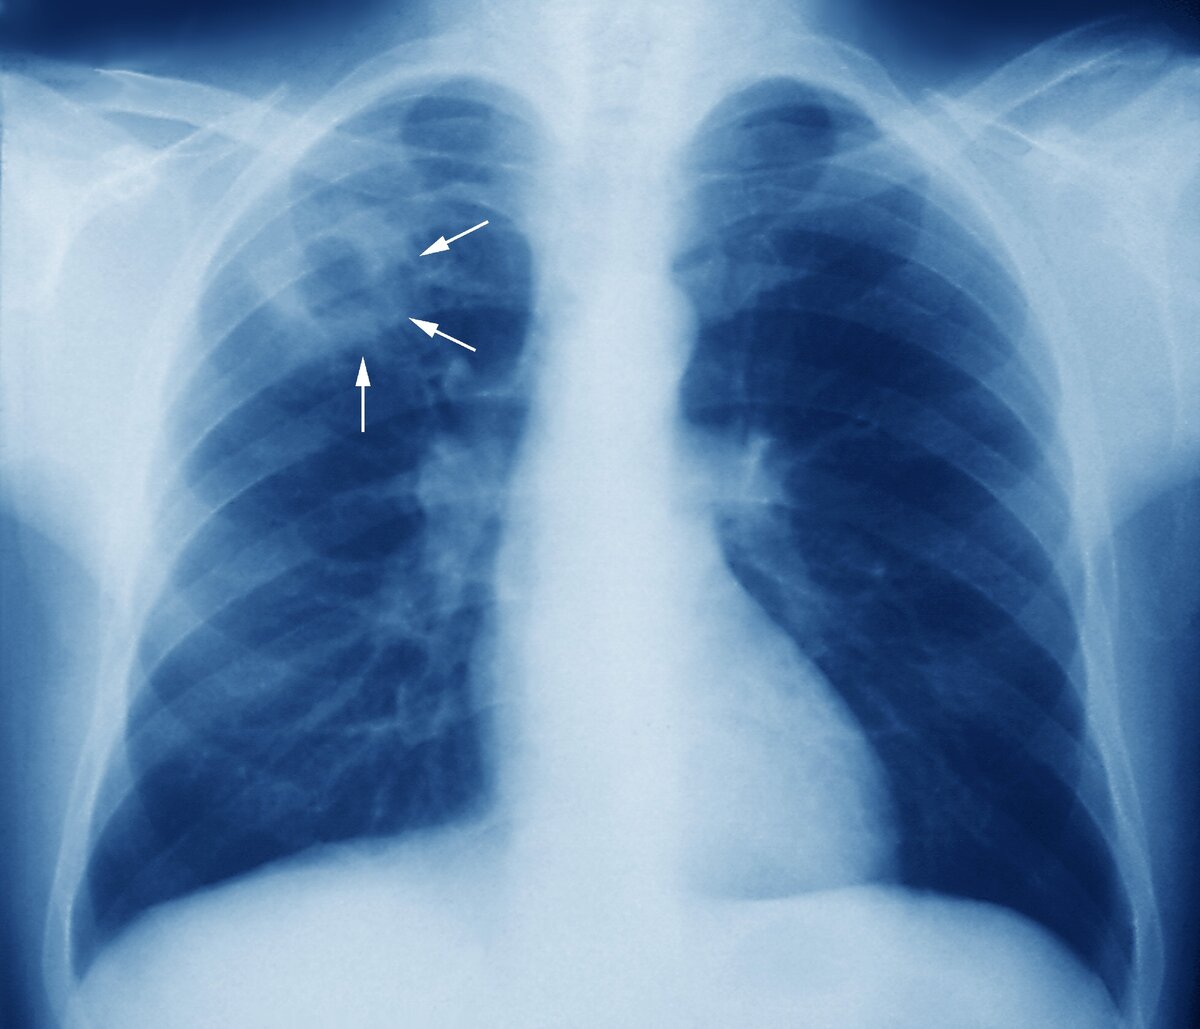

Первичный очаг Гона во всём его великолепии. Рентгеновский снимок взят из открытых источников. Только не нужно его искать на своих рентгеновских снимках. Он не всегда бывает именно такого вида.

По абсолютно ни для кого до сих пор неизвестным причинам у одних – он перерастает в реальное заболевание, а у других – абсолютно никак себя не проявляет до самой нашей смерти. Так что, потенциально: все мы – «чахоточники».